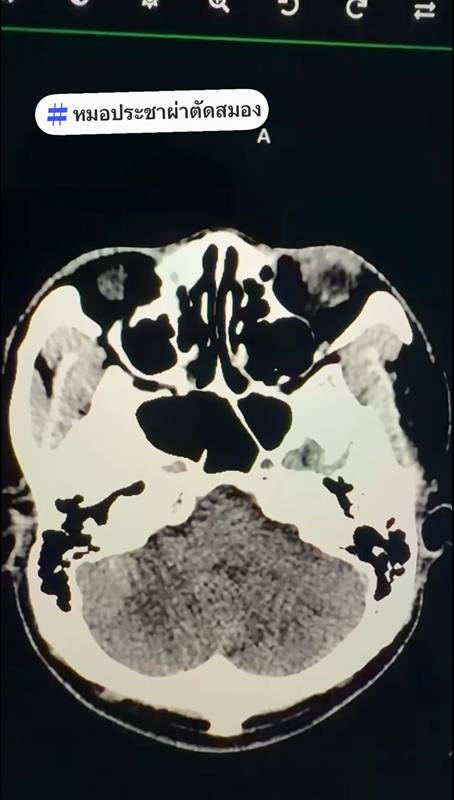

เคสแรก ผู้ป่วยชายอายุ 65 ปี มีแคลเซียมที่เกาะอยู่เต็มลำของหลอดเลือดเลี้ยงก้านสมองและซีรีเบลล่า จึงทำให้เคสนี้มีอาการเวียนหัวไม่หาย 1 สัปดาห์ก่อนมา ภรรยาสังเกตว่าเดินไม่ปกติ ทำ MRI ภรรยาบอกว่าหาสาเหตุไม่เจอ หมอทำการฉีดสีและทำ CTA จะเห็นแคลเซียมเกาะอยู่ที่ Vertebral artery แคลเซียมที่เกาะอยู่ 2 เม็ดนี้เป็นโรคหลอดเลือดสมองMRI ถ้าสมองยังไม่ตาย จะเห็นว่าปกติ ต้องดูหลอดเลือดถึงจะอธิบายอาการได้

แคลเซียมเกาะที่ผนังหลอดเลือด ทำให้รูของ Vertebral artery เล็กลง ขาดเลือด จึงทำให้เวียนศีรษะรุนแรง เดินเซ ทรงตัวไม่ได้ เหตุนี้ต้องทานยาต้านเกล็ดเลือดและยาลดไขมัน เพื่อป้องกันไม่ให้หลอดเลือดสมองตันถาวร เพราะตำแหน่งนี้ถ้าตาย ก็อาจเป็นเจ้าชายนิทราหรือเสียชีวิต

ภาพจาก เฟซบุ๊ก หมอประชาผ่าตัดสมอง

เคสที่ 2 ผู้ป่วยหญิงอายุ 55 ปี มึนหัวและปวดหัวตอนหลังตื่นนอนตอนเช้า เป็นมา 1 เดือนก่อนมา ทำ MRI พบว่าปกติ ก้านสมองและซีรีเบลล่ายังไม่ตาย มันแค่ขาดเลือด หมอทำการฉีดสี CTA หน้า ขวา หน้า ซ้าย หลัง ขวา หลัง ซ้าย ปรากฏว่าเคสนี้ถ้า Basilar artery ตัน ก็กลายเป็นเจ้าหญิงนิทราได้เลย มึนหัวทุกเช้า เพราะนอนกรนและหยุดหายใจตอนหลับ